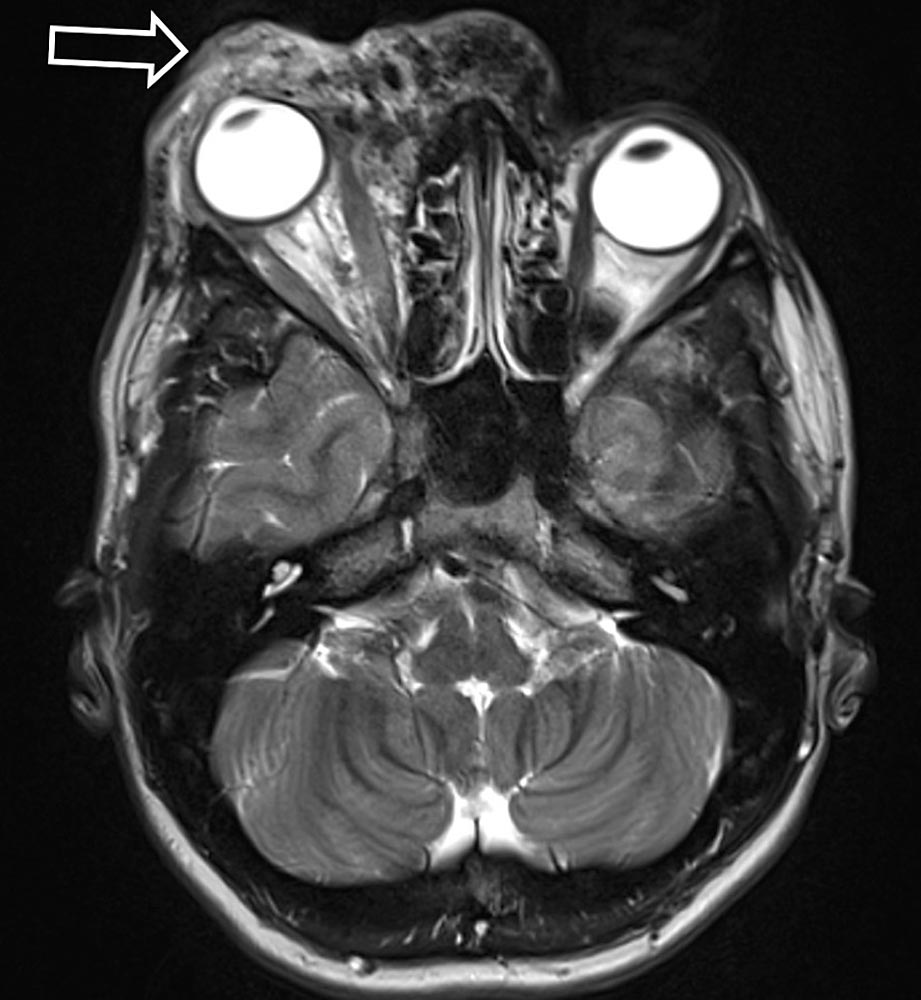

Die ersten Symptome sind meist das Vorhandensein einer Schwellung und ggf. eine leichte lokale Überwärmung mit rötlicher Verfärbung der Haut im Vergleich zum Umgebungsgewebe.

Durch die vorliegenden Shunts kann diese Schwellung mit einem Pulsieren sowie einer zunehmenden, sich ausbreitenden Überwärmung vergesellschaftet sein. Durch die erhöhte Volumenbelastung im venösen System können Symptome der chronischen venösen Insuffizienz hinzukommen. Sowohl venöse Insuffizienz als auch reduzierter arterieller Blutfluss peripher des Nidus können zu einer diffusen Schmerzausbreitung führen. Kompression oder Invasion des umgebenden Gewebes, hervorgerufen durch Shunts und dilatierte Gefäße, können zusätzlich Funktions- und Bewegungseinschränkungen (bspw. Muskelkontrakturen, Gelenk- oder Knochenbeteiligung) hervorrufen.

In Abhängigkeit von Angioarchitektur und Lokalisation können Blutungen, Ulcera und gangränöse Veränderungen auftreten. Kardiale Symptome treten entweder direkt nanch der Geburt oder erst in den fortgeschrittenen Krankheitsstadien in Erscheinung (Tachyarrhythmie, linksventrikuläre Hypertrophie und Dilatation).